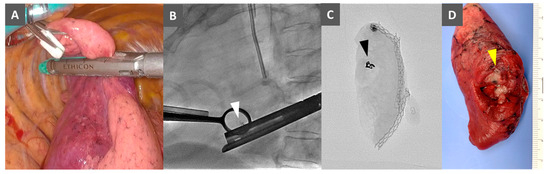

2.4. Bronchoscopic Metallic Coil Marking Procedure

2.5. VATS Resection Technique